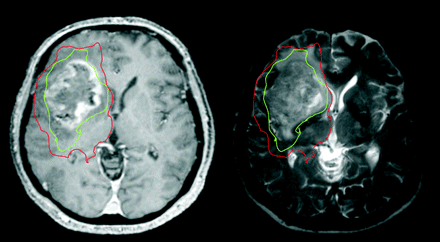

This study has shown that the abnormalities seen in the peritumoral region of gliomas when using diffusion tensor MR imaging are due to tumor infiltration. Furthermore, this study shows that this technique can define 2 regions around gliomas—an area with a decrease in the anisotropic component of the diffusion tensor tissue signature (q) more than our threshold of 12% that signifies the gross tumor and a region with normal q and an increase in the isotropic component, p, of greater than 10% of the normal side that signifies an area of tumor infiltration into normal brain. An example of such regions plotted on a gadolinium-enhanced T1-weighted image of a glioblastoma is shown in Fig 4.

A gadolinium-enhanced T1-weighted (left) and T2-weighted (right) image from a 67-year-old man who presented with headaches and a left hemiparesis. Our results have shown that we can identify a region around a tumor with decreased anisotropy (q, shown in green) that shows the limit of the gross tumor, and a region around this with normal anisotropy but increased isotropy (p, shown in red) that can identify the infiltrating tumor margin. These zones extend beyond the abnormal areas on both enhanced T1- and T2-weighted MRI